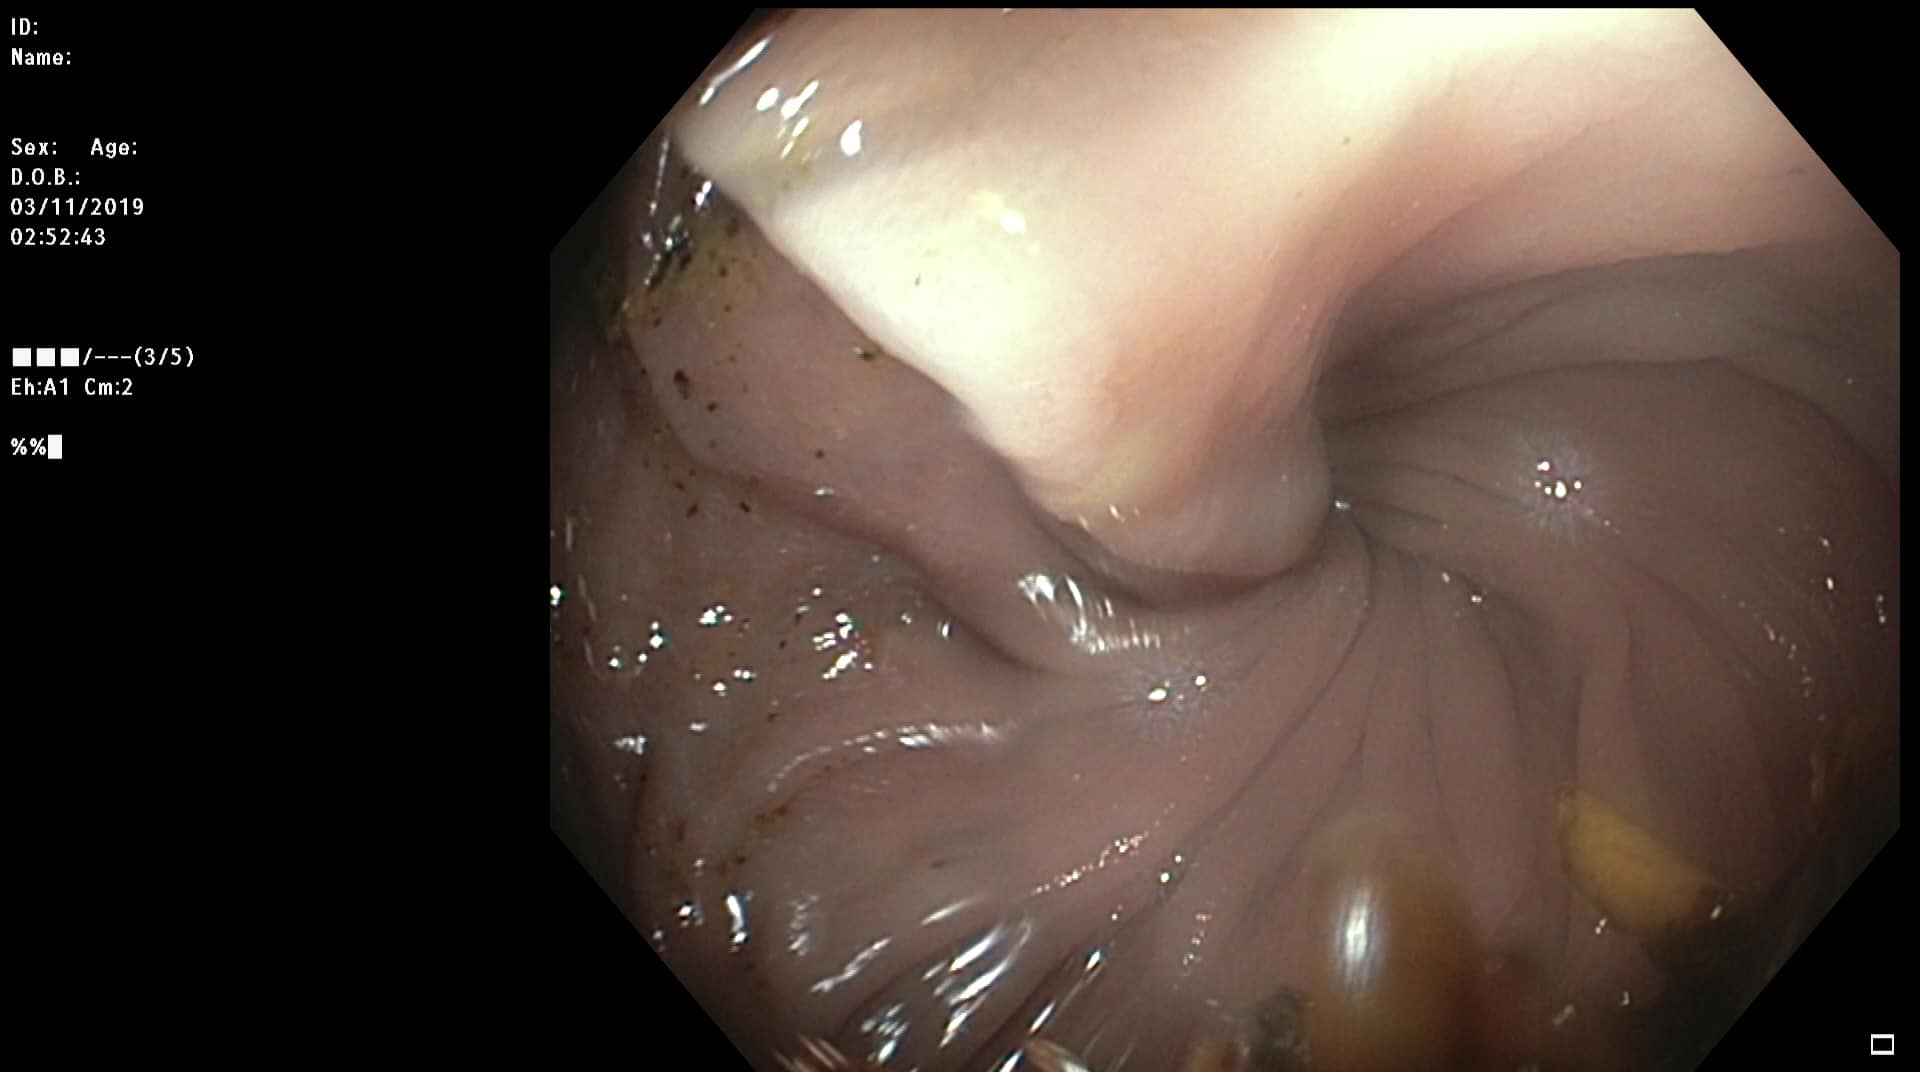

Tidligere frisk mann f.-33 som kom til koloskopi pakkeforløp pga magesmerter, endret avføring, Hb-fall tre enheter og pos hemofec. Trombocytopeni. Bedring etter oppstart PPI. Dag 1 dårlig tømt, kun distal skopi, men funn av stor polypp i venstre colon. Ved gastroskopi ulcerasjoner i tilheling. Dag 2 koloskopi med funn av atypiske polypøse lesjoner i mye av colon, både store og små. Bilde nr. 2 og 3: analt og oralt for sigmoideumvolvulus. Diagnose?